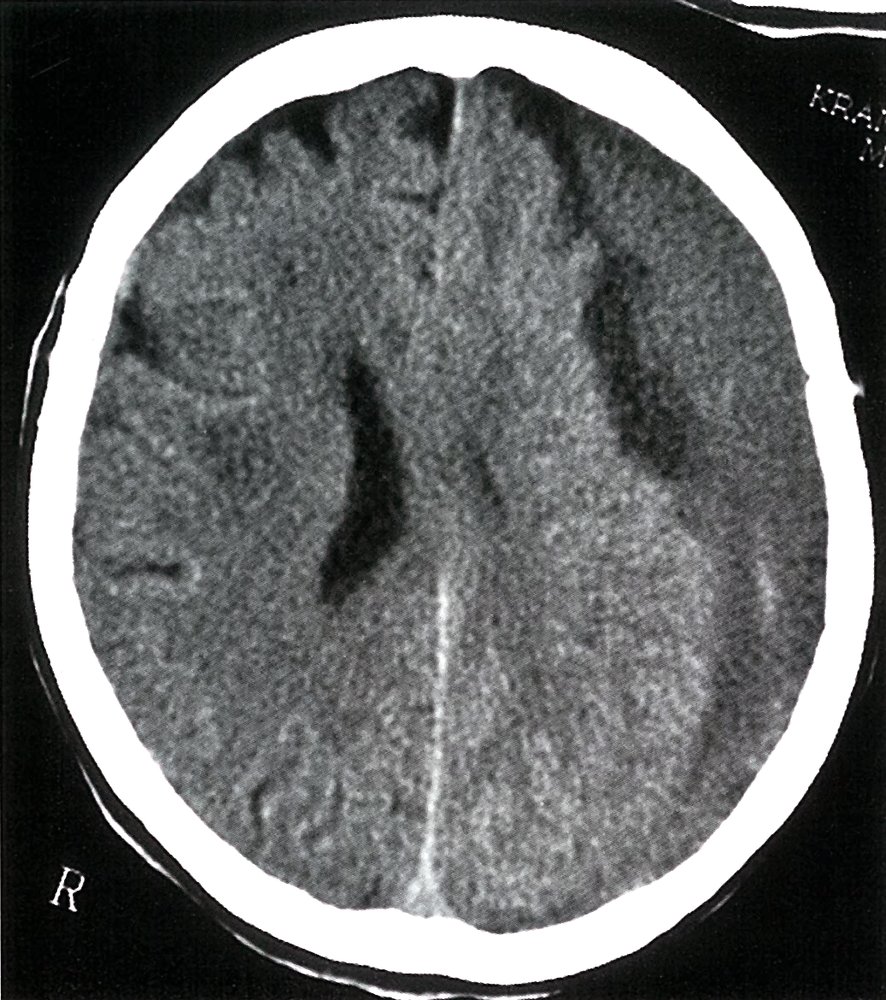

- An abnormal neurological status may be caused by:

Primary brain injury (e.g., stroke, TBI, status epilepticus)

- Systemic conditions (with or without secondary brain injury): see “Causes of AMS and coma.”

- Consider immediate neurology and/or neurosurgery consult for suspected acute stroke, intracranial bleed, or cerebral herniation.

Neuroimaging: e.g., CT head

Stroke (hemorrhagic or ischemic)